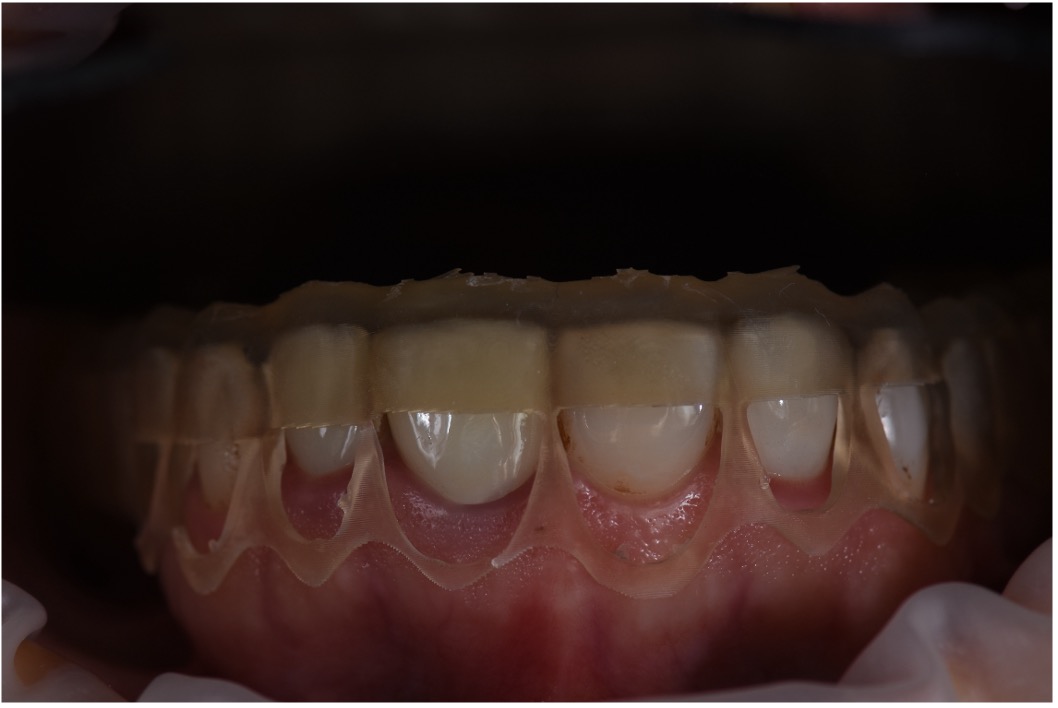

Once the digital design was approved, a physical mockup was created using resin for 3Dprinted materials. This mockup served as a test-drive for the proposed outcome, enabling real-time evaluation of the smile design in terms of esthetics, speech, and occlusion. The mockup was fitted in the clinic and reviewed from multiple angles, with special attention given to the patient’s reaction and comfort. Adjustments were made accordingly, allowing for refinements before any irreversible procedures were performed.

Step 3: Interdisciplinary Treatment Planning

Following mockup approval, the clinical team proceeded with a detailed treatment plan

involving both surgical and restorative phases. The periodontist performed gingival recontouring to reduce the gummy smile and define ideal gingival margins. Diagnostic wax-ups and CBCT scans were essential tools in guiding this stage, helping to visualize bone levels, tooth proportions, and soft tissue behavior. A surgical guide was fabricated in this stage to showcase the amount of gum that will be removed to reach the digital smile design phase